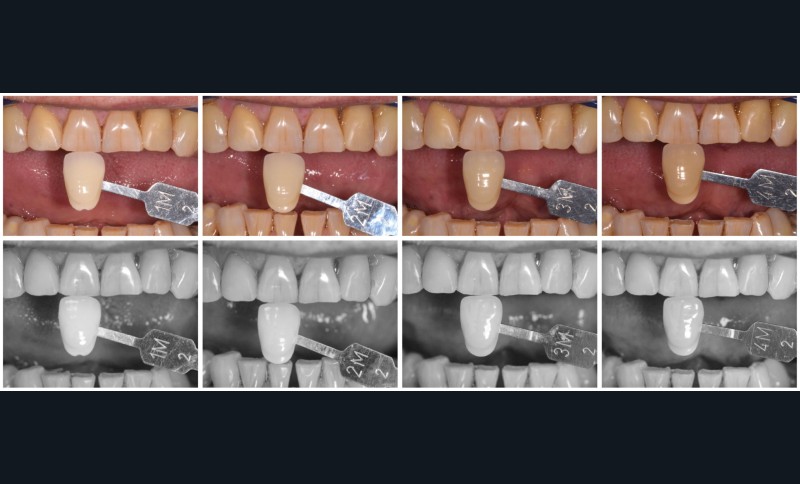

La proposition thérapeutique retenue par le patient est donc une réhabilitation par couronne céramique sur 12 (dento-portée) et 22 (implanto-portée). Ce choix thérapeutique impose de concevoir des dents qui s’intègrent au mieux dans l’harmonie du sourire, tout en étant conscient des limites d’un tel traitement.